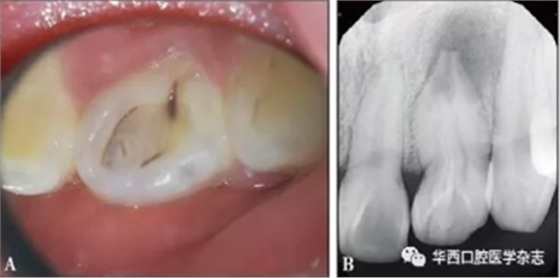

患者萬(wàn)某,女,21歲,2017年3月26日因左上前牙偶發(fā)脹痛不敢咬合數(shù)年于南昌大學(xué)附屬口腔醫(yī)院牙體牙髓科首診。口內(nèi)檢查:22牙唇側(cè)牙冠顏色、形態(tài)無(wú)異常,舌側(cè)中央內(nèi)陷,下方呈黑褐色,舌隆突處凹陷未蔓延至齦下(圖1A),唇舌側(cè)牙齦色澤形態(tài)質(zhì)地均無(wú)明顯異常,未見(jiàn)瘺管,叩診陽(yáng)性,牙周探診6個(gè)位點(diǎn)探診深度均小于3 mm,無(wú)附著喪失,無(wú)松動(dòng);牙髓電活力測(cè)試,12牙讀數(shù)17(上限64),21牙讀數(shù)20(上限64),22牙無(wú)反應(yīng);牙髓溫度測(cè)試,12牙、21牙冷熱診反應(yīng)一過(guò)性敏感,22牙冷熱診無(wú)反應(yīng)。X線片示22牙根管彎曲,牙冠內(nèi)陷從釉質(zhì)延續(xù)至根中1/3,主根管中央有一“內(nèi)陷小牙”高密度影結(jié)構(gòu),內(nèi)陷組織遠(yuǎn)中與主根管間可見(jiàn)明顯間隙,根尖孔粗大,根尖區(qū)為邊界不規(guī)則低密度影像,未見(jiàn)牙槽嵴頂處骨高度吸收異常(圖1B)。

A:口內(nèi)照;B:X線片。

圖 1 治療前情況